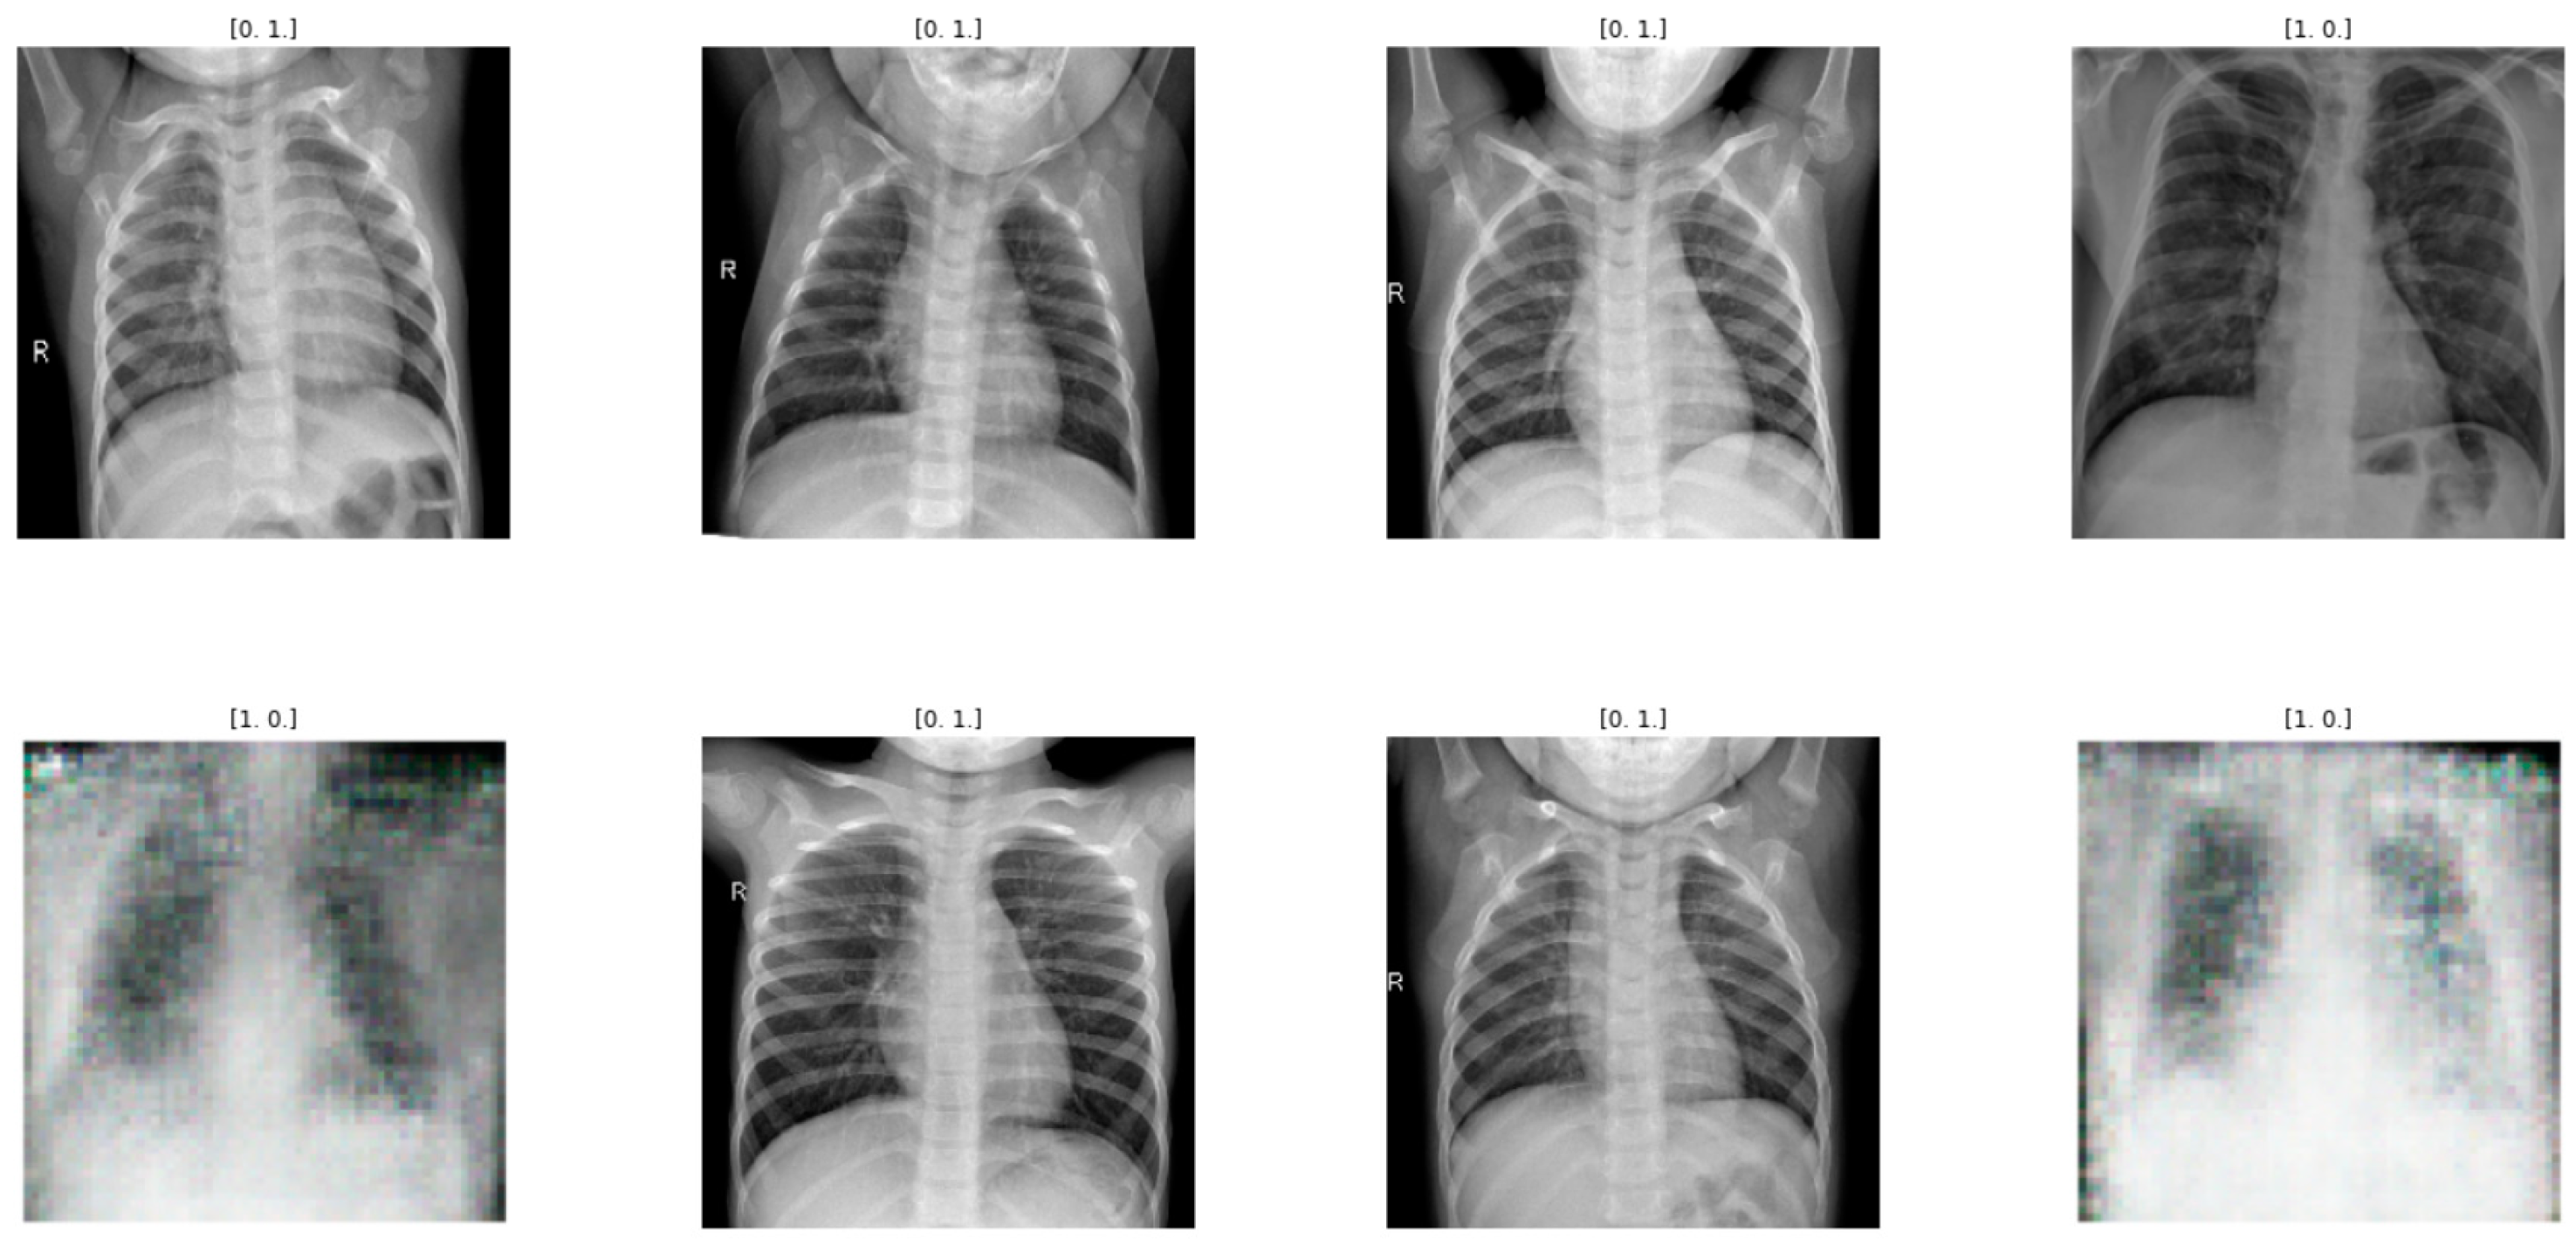

To address the aforementioned challenges, researchers and practitioners have developed an automated detection system for coronavirus infections using artificial intelligence (AI) techniques [10]. In the past decade, the combination of AI with medical imaging has aided several industries, including healthcare, in diagnosing and treating a variety of conditions. Deep Neural Networks [11] are being utilised in the healthcare sector as of late. The Convolutional Neural Network (CNN) is a well-known Deep Neural Network. Deep learning models were successfully applied in a variety of fields, including medical data segmentation, classification, and lesion identification [12]. In battling with COVID-19, respiratory symptoms are one of the most common COVID-19 symptoms, and they may be detected through chest X-ray imaging. A condition with modest symptoms may also be diagnosed using chest CT scans. Typically, detection is accomplished by analysing indicator data (Mohsin Ahmed and Wael Abdullah, 2021). For the CNN to detect a coronavirus infection from chest X-ray images, massive amounts of training data are required. However, adequate chest X-ray image datasets with equal COVID-19 and normal chest images are unavailable. The absence of supervised data may contribute to the class imbalance issue [13]. As a result, there is a strong need to broadly automate such operations, and they should be available to everyone so that diagnosis may become more efficient, accurate, and rapid. Imaging is the fastest and most accurate way to detect COVID-19. Researchers use X-ray images for COVID-19 detection because of their benefits. Low cost and wide availability are its main advantages over other imaging methods. Furthermore, X-ray imaging uses less radiation than CT scan imaging. It detects lung cancer and cardiac diseases. X-ray images are widely used, especially in poor countries. CT scans are better than X-rays [14]. CT scans provide more accurate diagnoses. CT scans are expensive and expose patients to more radiation. CT and X-ray images are popular for COVID-19 identification. Ground-glass opacification in the upper right lung is seen in X-rays. CT scans use ground-glass areas in the lower lung and halo signs and consolidation areas in the lower lobes [15,16,17,18]. X-ray and CT imaging features of COVID-19 and non-COVID cases are shown in Figure 1 [19].

To assist with the sampling and generation of data for the two models, the author develops three straightforward functions. In the first, real images are taken as samples from the training data, in the second, random vectors are drawn from the latent space, and in the third, latent variables are fed into a generator model to produce generated fake examples. Fake (generated) images are created once the models have been trained on the COVID and normal datasets, as shown in Figure 5 and Figure 6, and they are saved in a folder created for the further computational process.

The GAN models we developed are evaluated using accuracy and other measurements from the confusion matrix. Figure 5 and Figure 6 show some fake (generated) images created after training the model for 2000 epochs on the COVID and normal datasets.

Figure 1. Images for chest X-ray and CT images for COVID-19 [19].

Figure 5. GAN model being trained for COVID dataset.

Figure 6. GAN model being trained for normal dataset.

Figure 7. The proposed VGG16 CNN-GAN model is being trained for COVID dataset.